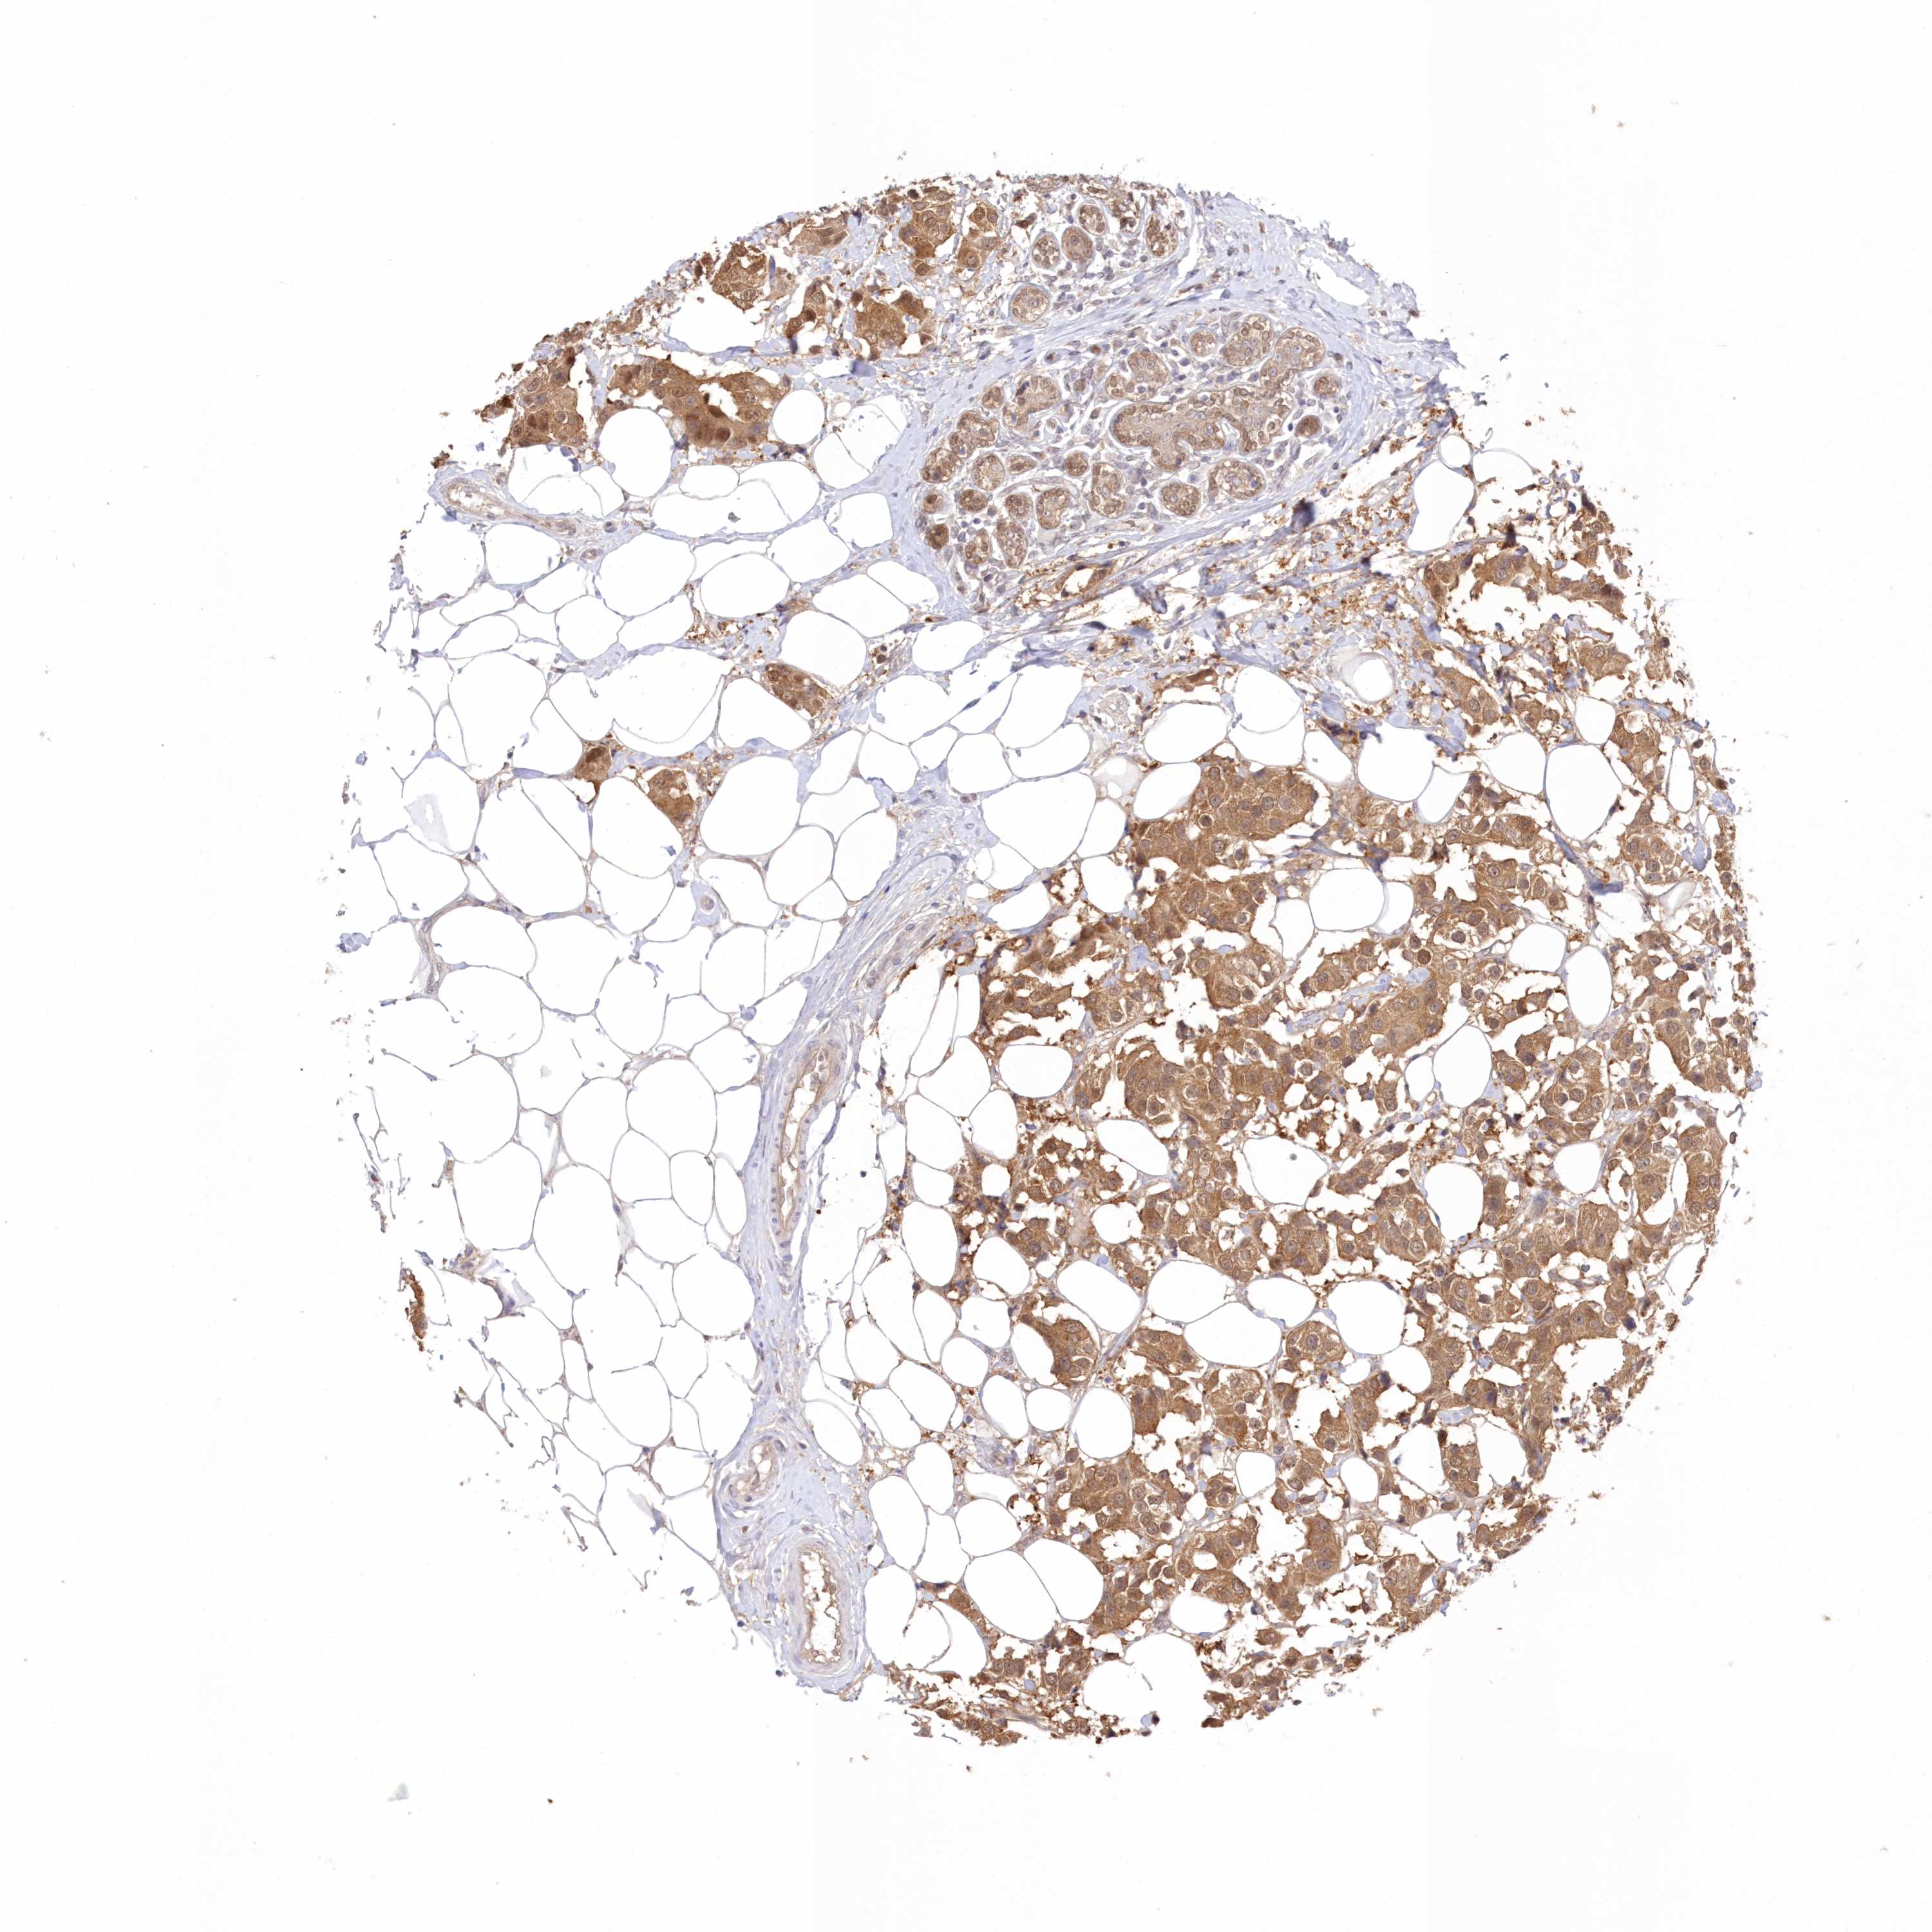

CANCER BREAST CANCER Show tissue menu

BRCA TCGA BRCA VALIDATION PROTEIN EXPRESSION

Breast cancer

Human cancer